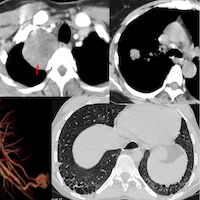

56-years old with an incidentally detected lung nodule in the superior segment of the right lower lobe of the lung. It showed one calcific speck. No contrast. No PET. There was extrapleural fat retraction, suggesting this could be extra-pulmonary.

On biopsy, it was firm. Histopath shows cartilage.

This is a peripheral chondroid hamartoma of the lung. Likely so longstanding, that the pleura has puckered around it.

Similar case.